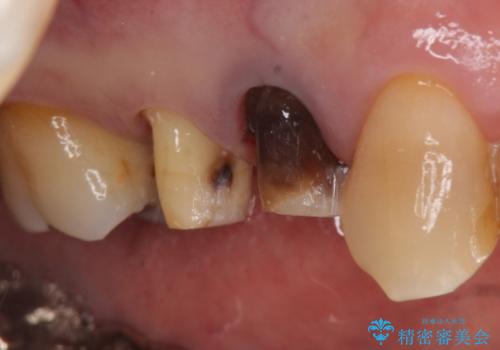

- 右上4番目の歯が黒くなっているのが気になるといらっしゃった方の症例です。

再根管治療後、オールセラミッククラウンによる補綴を行いました。

右上5も虫歯があったためオールセラミッククラウンによる補綴を行っております。